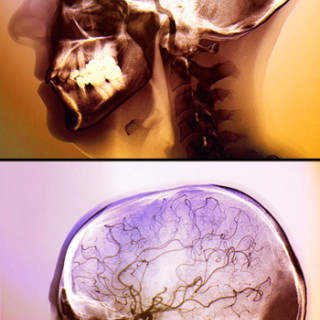

I USA er forekomsten av hjerneslag hos mennesker over 65 år gått ned de siste tiårene. I en studie som omfattet over 14 000 personer i fire byer i USA, ble det i perioden 1987 – 2011 registrert litt over 1 000 nye tilfeller av hjerneslag, hvorav nesten 90 % var iskemiske (1). Aldersjusterte insidensrater for en tiårsperiode var 0,69 (95 % KI 0,59 – 0,81) i aldersgruppen over 65 år og 0,97 (95 % KI 0,76 – 1,25) for dem under 65 år. Samlet gikk dødeligheten etter hjerneslag ned for hver tiårsperiode med en hasardratio på 0,80 (95 % KI 0,66 – 0,91). – Denne kohortstudien fra USA viser at...